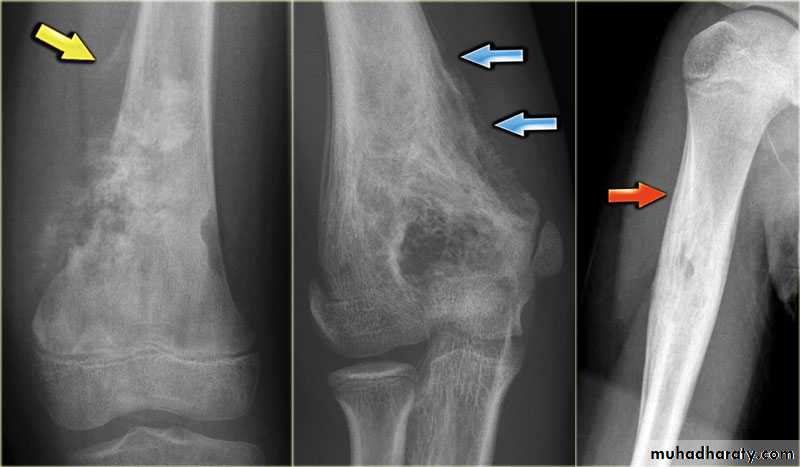

Primary malignant tumoursOsteosarcoma ( osteogenic sarcoma )

Giant cell tumour

Benign tumour & tumour like condition

Enchondromas :Fibrous cortical defects ( non ossifying fibromas )

Fibrous dysplasia :

5. Calcific densities within the lesion

6. Soft tissue swelling